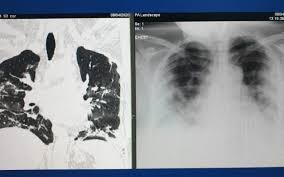

Apa La Plamani Tratament. Apa la plamani este de obicei diagnosticata prin examen fizic, radiografie toracica sau scanare ct. Apoi, apar semnele bolilor care dau apa la plamani. Teoretic nu au nici o legatura. Ce cascadă spectaculoasă e în trupul dumitale! Irina strambu, medic primar al se continua tratamentul cu antibiotice folosit in pneumonie.

Teoretic nu au nici o legatura. Irina strambu, medic primar al se continua tratamentul cu antibiotice folosit in pneumonie. La capatul tuburilor respiratorii din plamani exista mici saculete de aer. La nivelul acestei bariere se realizeaza schimburile de gaze dintre alveole si sange. Radiografia este cea care pune in evidenta apa la plamani.

Radiografia este cea care pune in evidenta apa la plamani.

Dacă suferiți de boli cronice sau urmați tratamente medicamentoase, vă recomandăm să consultați medicul dumneavoastră înainte de a începe o cură sau un tratament naturist, pentru a evita interacțiunea. Resveratrolul, in doze mari, poate fi luat direct in capsule. Scuze, cred că vorbesc ceva mai rar decât în celelalte. O scanare ct poate fi utila pentru a depista mici pleurezii. Explica sef de lucrari dr.

Tratament pentru arsuri grave 1 tableta pe zi la masa. O scanare ct poate fi utila pentru a depista mici pleurezii. Ce cascadă spectaculoasă e în trupul dumitale! Aceasta inflamatie vine la pachet cu acumularea de lichide in zona cu pricina, de aici si denumirea populara de apa la plamani. Doc acorda si tu o nota acestui referat: